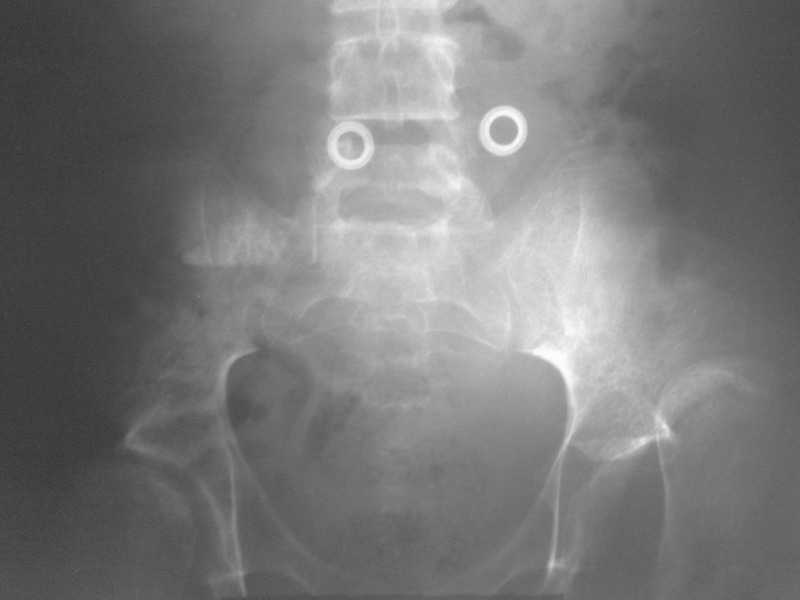

Под общим наркозом вправлен. 2 недели ребенок находился на лейкопластырном вытяжении. В связи с тяжким состоянием ребенка (диспептические явления, задержка стула, носовые кровотечения, начальные явления застойной пневмонии) вытяжение снято. сразу после чего сделано рентген контроль (фото 1). а через неделю, то есть сегодня сделан второй снимок (фото 2). Где видно повторный вывих.

На рентгенограмме видно, что в 3 месячном возрасте не была диагностирована тяжелая форма дисплазии с подвывихами, где, кроме вывиха, имеет место непролеченные диспластические суставы с обеих сторон, больше справа.